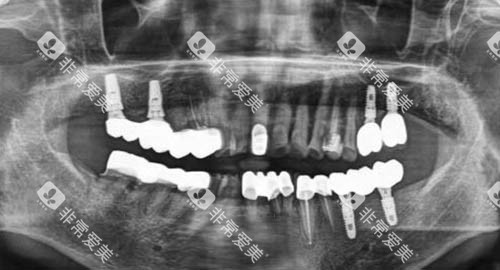

如智能化口腔全景机,它能够快速、较准地拍摄口腔全景图像,为医生诊断病情提供详细的依据;种植机则具备高精度的操作性能,大大提高了种植牙手术的成功概率。